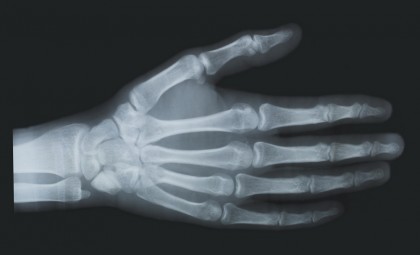

Radiografia mâinii, în special, relevă numeroşi centri de osificare, cu progresie în timp şi este standardul pentru estimarea vârstelor osoase la copiii mai mari de 3 ani. Copiii şi sugarii sub 3 ani au modificări la nivelul genunchiului care pot fi mai uşor de apreciat. Prin urmare, radiografiile genunchiului sau chiar ale hemischeletului sunt folosite pentru copiii mici.

Oasele de pe imaginea radiografică sunt comparate cu imaginile radiografice dintr-un atlas standard de dezvoltare osoasă, care se bazează pe date de la un număr mare de alţi copii de acelaşi sex şi vârsta. Vârsta osoasă a unui copil poate aprecia sau nu vârsta cronologică a acestuia (vârsta reală în ani în funcţie de data naşterii sale). Printre factorii care influenţează progresia dezvoltării scheletului sunt: nutriţia, genetica, hormonii şi, nu în ultimul rând, bolile asociate. [1] [2]

Baza evaluării maturarii scheletului constă în modificările previzibile care apar în timp la nivelul centrelor de osificare. Oasele lungi, inclusiv osul ulnar, radiusul şi falangele cresc până când capetele oaselor (epifizele) fuzionează cu metafizele. Această fuziune a plăcii de creştere nu se întâmplă în acelaşi timp în mod uniform în corpul unui copil.